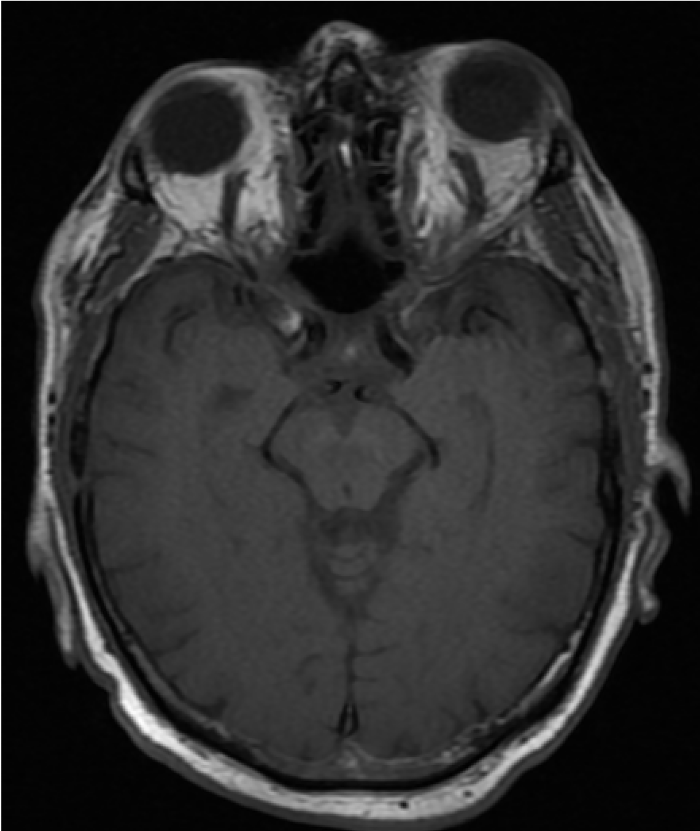

Most patients initially undergo noninvasive imaging with computed tomography (CT), magnetic resonance imaging (MRI), CT angiography (CTA), or magnetic resonance angiography (MRA). The most common neuroimaging signs of anterior draining CCFs include proptosis, enlargement of the SOV, CS, and extraocular muscle enlargement.[30] Enlargement of the IOV and cerebral venous congestion can also seen. If there is a high degree of clinical suspicion or suggestion of a CCF on noninvasive imaging, diagnostic cerebral angiography (digital subtraction angiography, DSA) can confirm the diagnosis and guide treatment.

MRI: Compared to CT, MRI can better demonstrate fat stranding reflecting orbital edema and abnormal flow voids.[33]